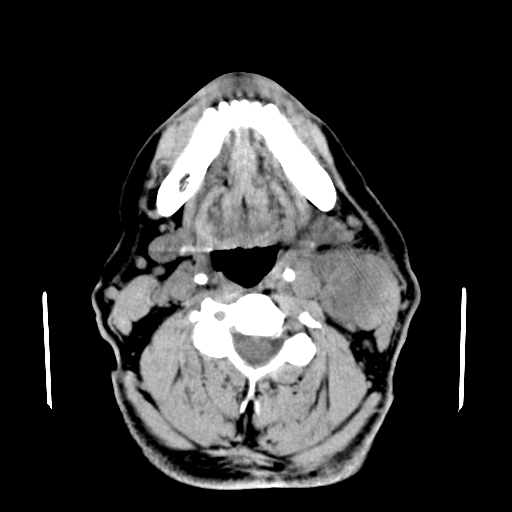

以下是引用卜一在2007-8-6 21:23:00的发言:[br]定位:左侧胸锁乳突肌内侧 颌下腺下后方。特征:弥漫性生长 软组织密度肿块,界限不清,内隐约见低密度坏死。考虑:神经源性肿瘤或血管源性肿瘤。

以下是引用wangzhanshuang在2007-8-6 21:08:00的发言:[br]腮腺混合瘤